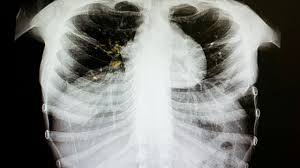

A tuberculosis outbreak has been officially declared in Edmonton, affecting the city’s inner-city and homeless population. Health authorities confirmed that the outbreak was identified after two individuals living in central Edmonton were found to be infected with the same strain of TB, indicating recent local transmission. This announcement came from Primary Care Alberta’s tuberculosis program, in coordination with Edmonton zone medical officers of health, in October 2025.

Tuberculosis, commonly known as TB, is a preventable and treatable bacterial infection that primarily attacks the lungs but can affect other parts of the body. It spreads through the air when someone coughs, sneezes, or spits, making close contact a key risk factor. While TB can be successfully treated with antibiotics, the World Health Organization still reports that around 1.5 million people die from the disease globally each year, making it the leading infectious killer worldwide. The infection is also particularly dangerous for people living with HIV and contributes to the growing problem of antibiotic resistance.